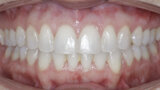

New Age orthodontics and orthopaedics with temporary anchorage devices